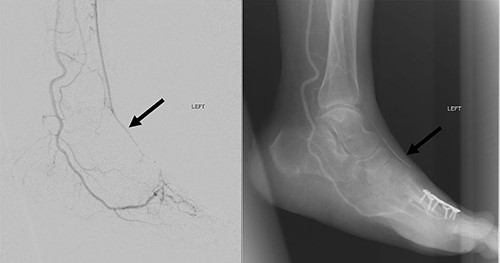

Good arterial flow of the ATA (arrow) after successful angioplasty and stenting.

Arterial flow noted at distal ATA and dorsalis pedis artery (arrow) after successful angioplasty and stenting.